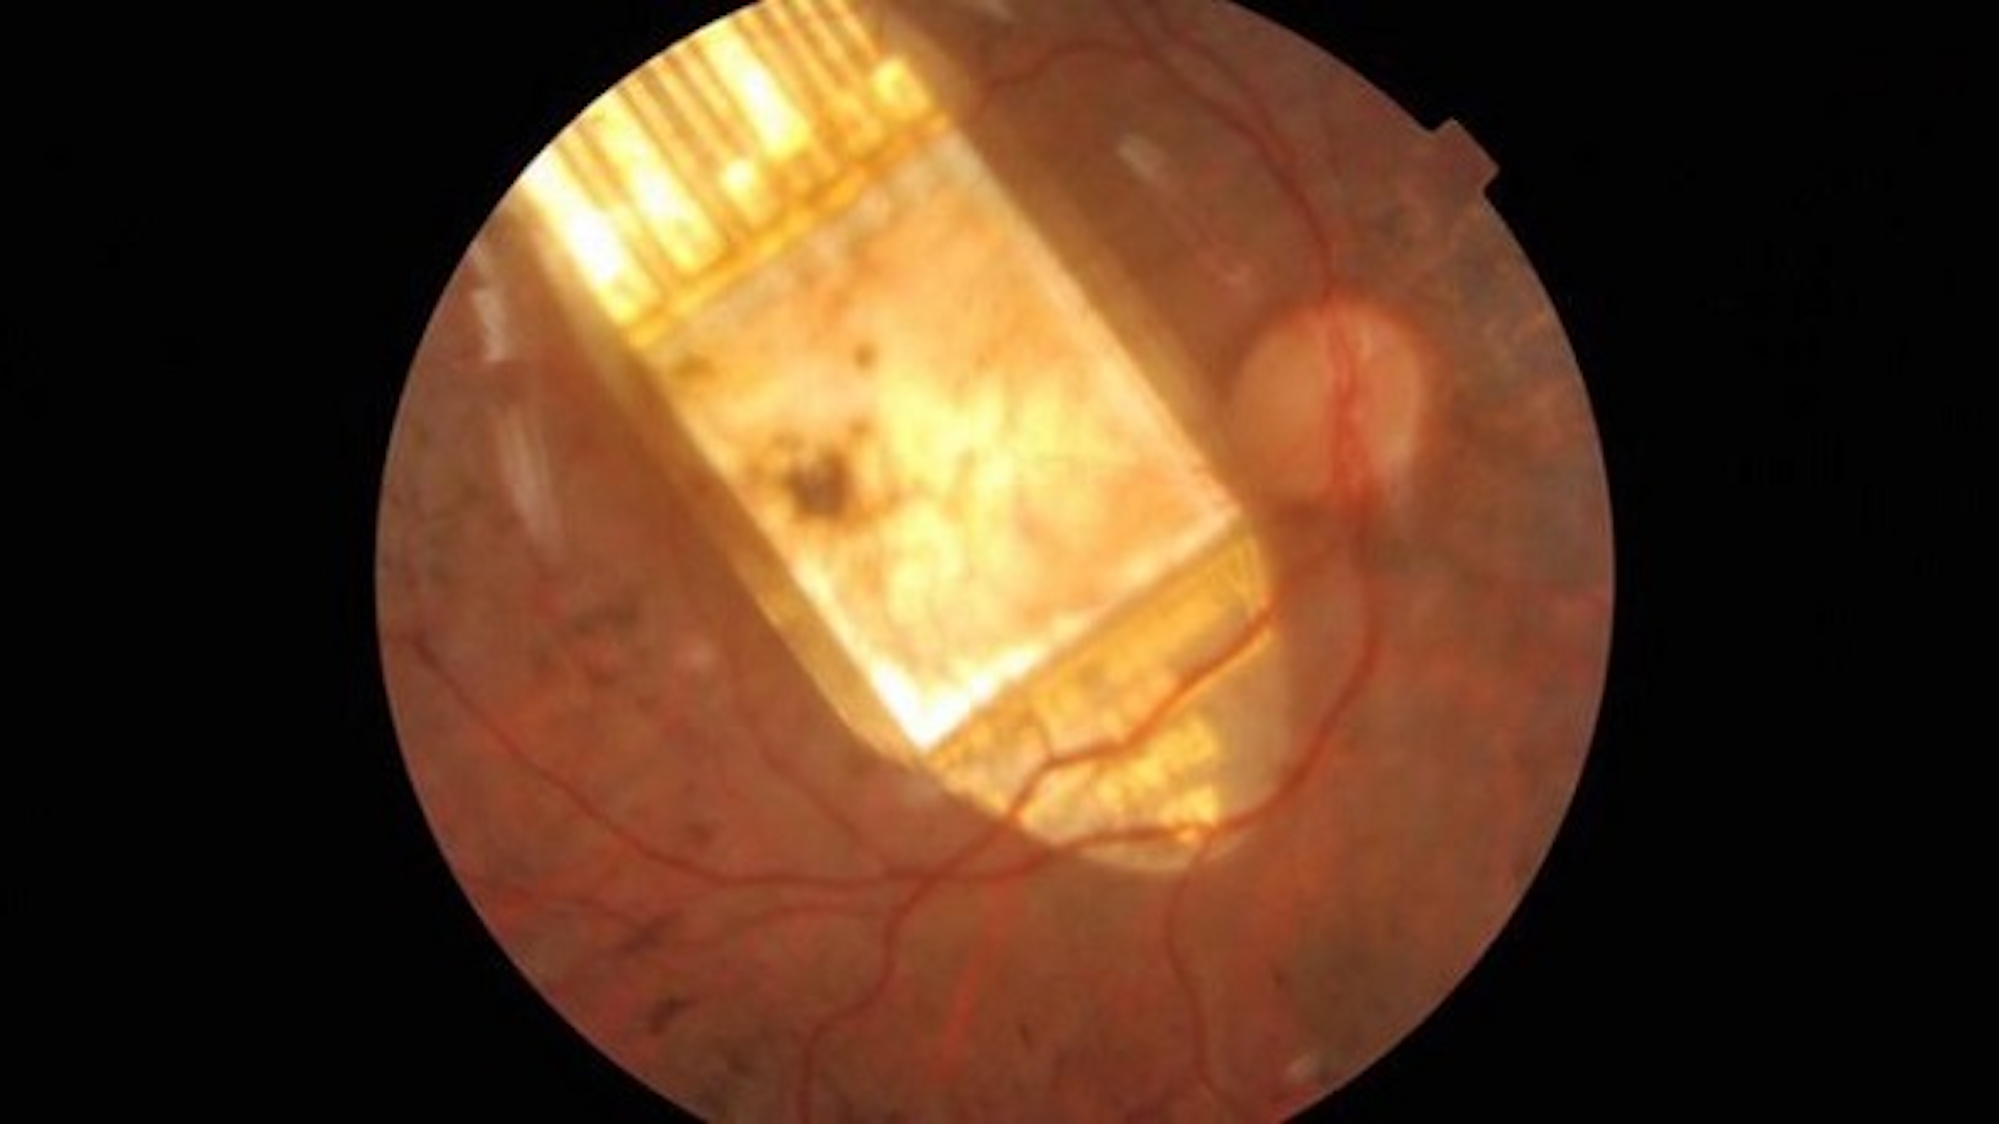

Optobionics was the first company to develop a subretinal implant and evaluate the design in a clinical trial. Initial reports indicated that the implantation procedure was safe, and all subjects reported some perception of light and mild improvement in visual function. The current version of this device has been implanted in 10 patients, who have each reported improvements in the perception of visual details, including contrast, shape, and movement. Retina Implant AG in Germany has also developed a subretinal implant, which has undergone clinical testing in nine patients. Trial was put on hold due to repeated failures. The Retina Implant AG device contains 1500 microphotodiodes, allowing for increased spatial resolution, but requires an external power source. Retina implant AG reported 12 months results on the Alpha IMS study in February 2013 showing that six out of nine patients had a device failure in the nine months post implant Proceedings of the royal society B, and that five of the eight subjects reported various implant-mediated visual perceptions in daily life. One had optic nerve damage and did not perceive stimulation. The Boston Subretinal Implant Project has also developed several iterations of a functional subretinal implant, and focused on short term analysis of implant function. Results from all clinical trials to date indicate that patients receiving subretinal implants report perception of phosphenes, with some gaining the ability to perform basic visual tasks, such as shape recognition and motion detection.